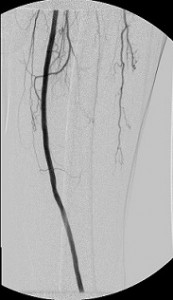

The images in the top panel illustrate multicentric moderate and severe (>50%) narrowings of the proximal left common femoral artery (LCFA) – not shown – and the superficial femoral artery and a focal critical stenosis of the proximal left tibioperoneal trunk in an elderly diabetic man with a chronic ulcer of his left foot. Notice that the critical tibioperoneal stenosis limits blood flow into the patient’s only named branch of his left popliteal artery, the peroneal artery, which is the principal path of blood inflow to the foot. Note, too, the severity of the lack of perfusion of the foot as shown by the “whiteness” of the patient’s hind foot.